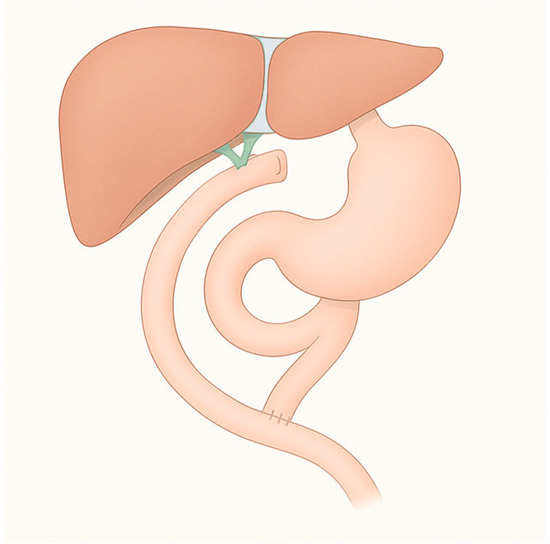

3.3. Roux-en-Y Gastric Bypass (RYGB)

RYGB is the most widely performed bariatric procedure worldwide. It consists of creating a small gastric pouch anastomosed to the jejunum, bypassing the excluded stomach and duodenum (Figure 3). This operation was originally designed for weight loss but is now equally valued for its metabolic benefits in patients with type 2 diabetes and severe obesity. Variations in limb length are frequent: long biliopancreatic or alimentary limbs are often employed in super-obese patients or those with severe metabolic disease to increase malabsorptive effects. An alternative is the mini-gastric bypass, in which a long gastric pouch is anastomosed directly to a jejunal loop. Despite its effectiveness in reducing calorie intake and weight loss, it carries the risk of bile reflux, which remains a subject of ongoing debate and study [8].

Figure 3. Gastric bypass.